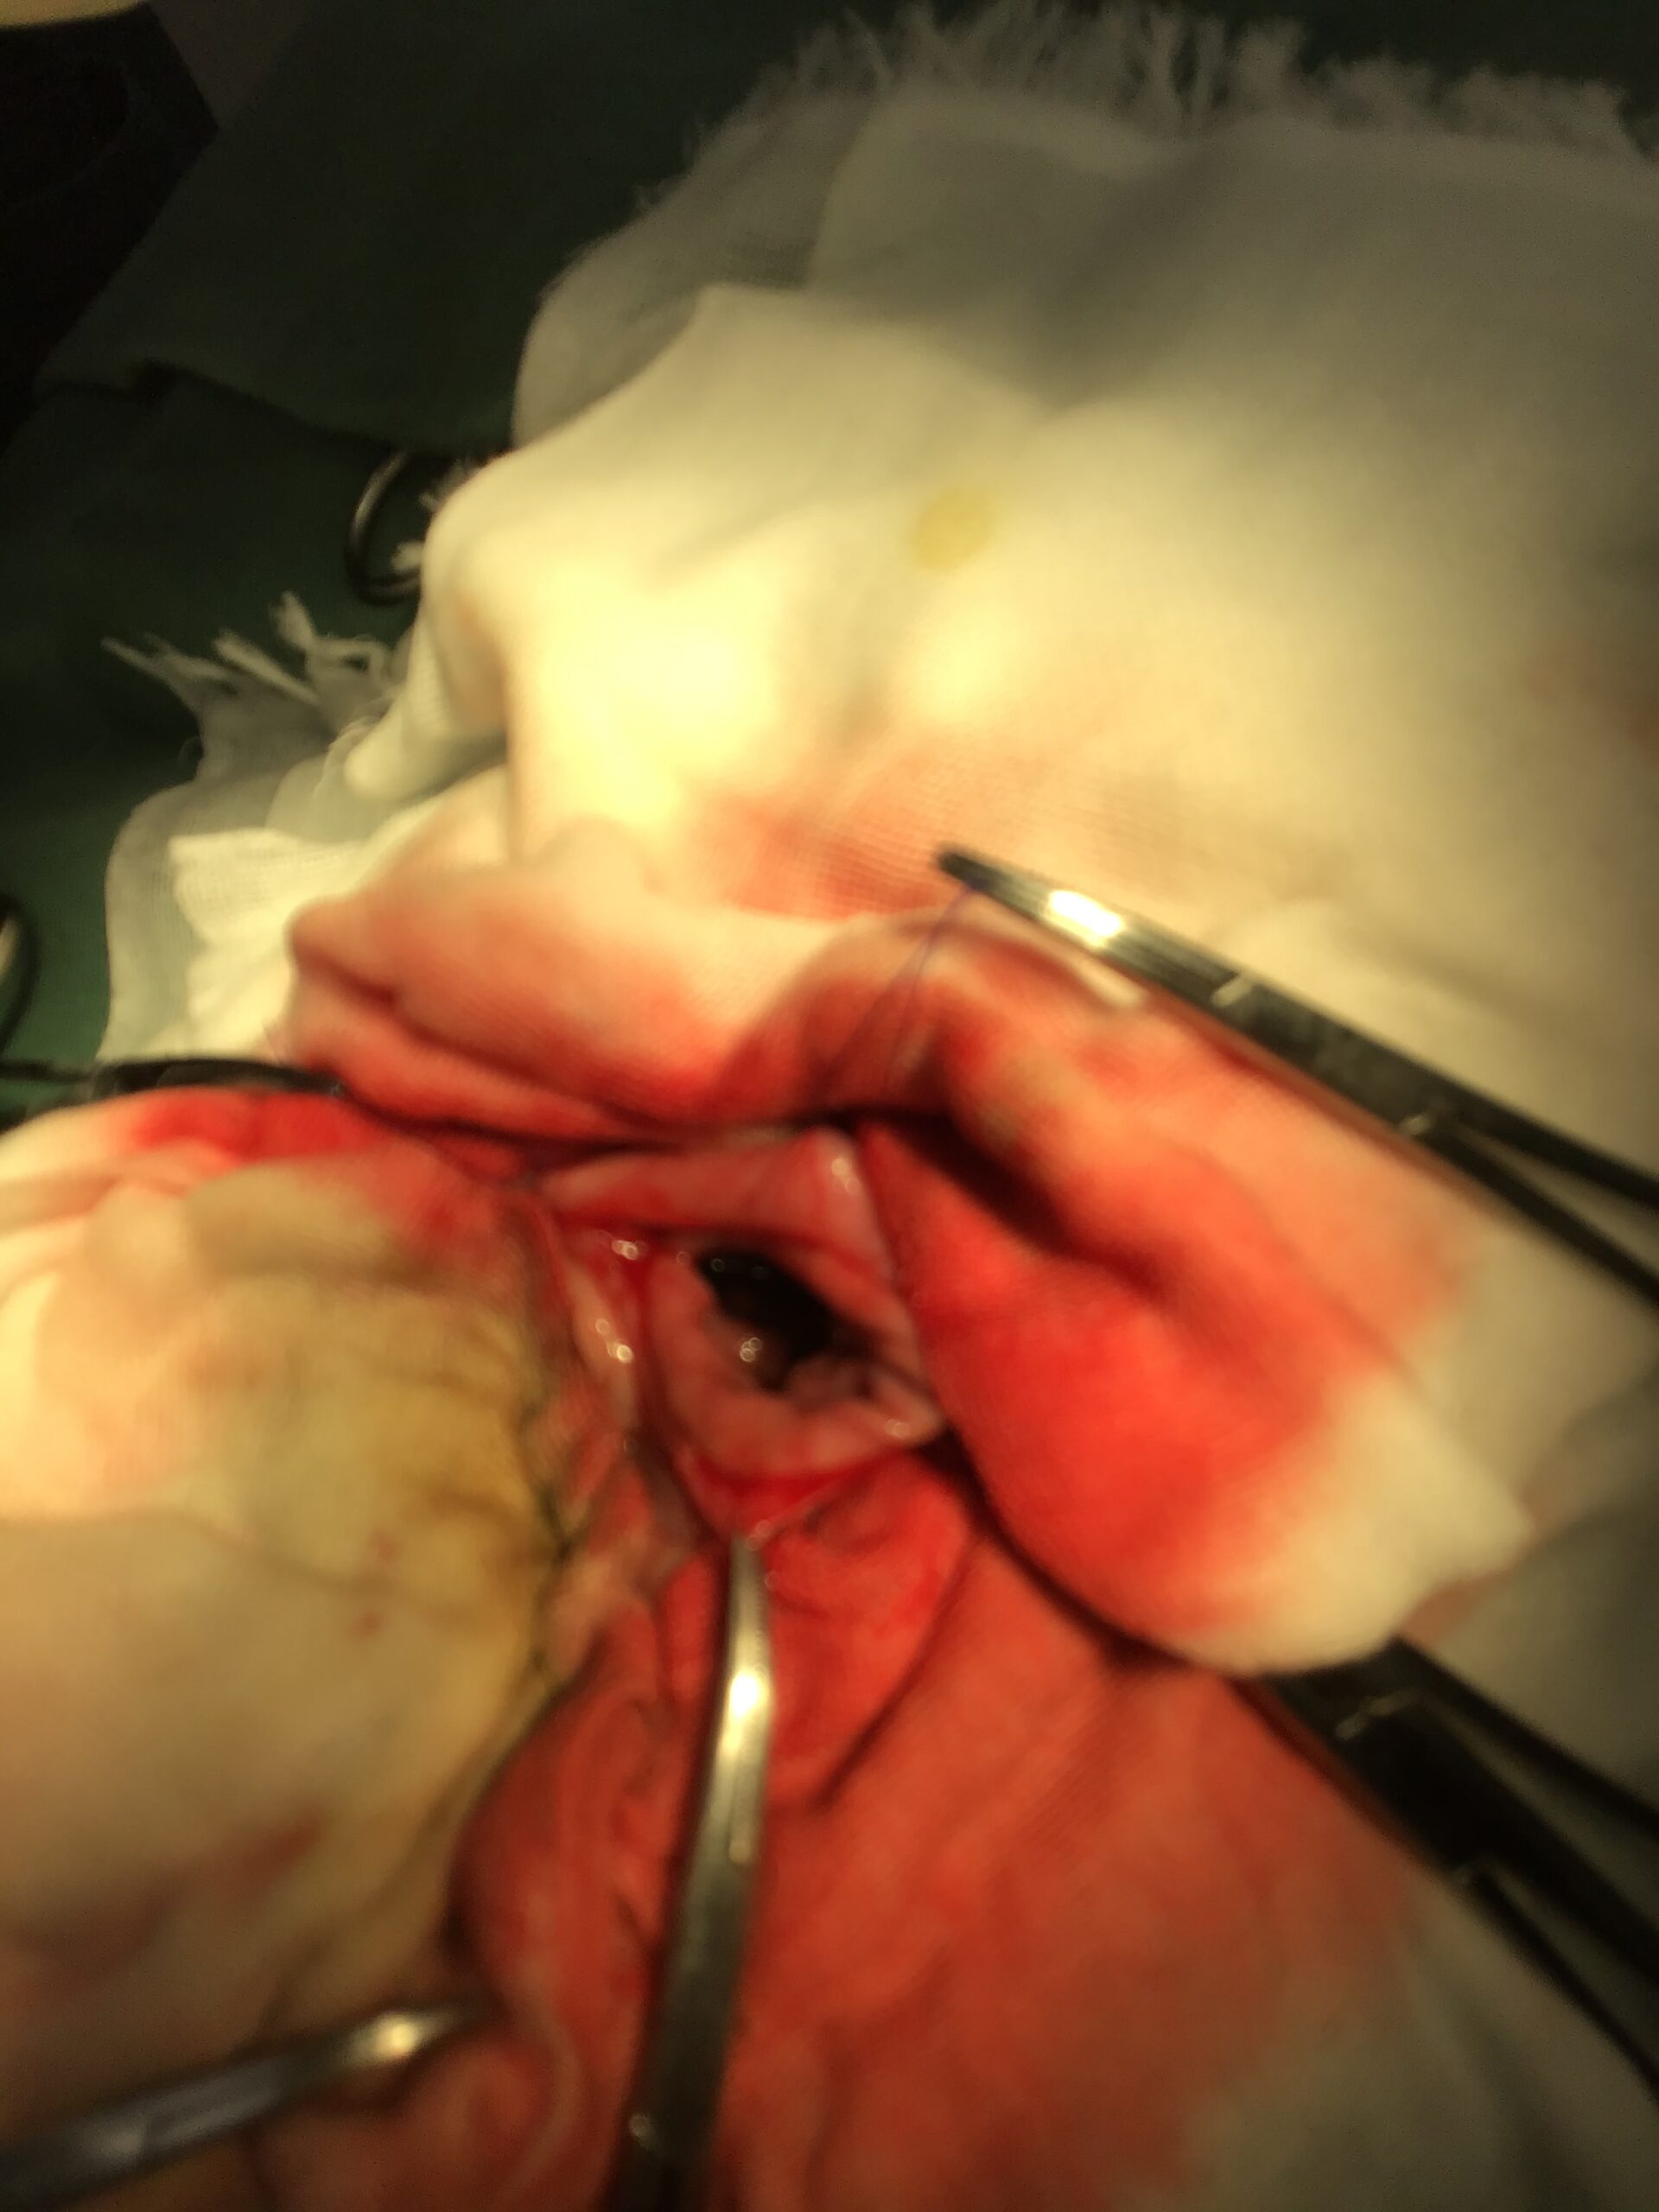

最悪の事態を防ぐため、緊急で胃および十二指腸の切開手術を実施して異物を摘出しました。術前・術中には、膵炎の治療薬や制吐剤、抗生剤を点滴で持続的に投与し、全身状態を安定させながら慎重に手術を進めました。